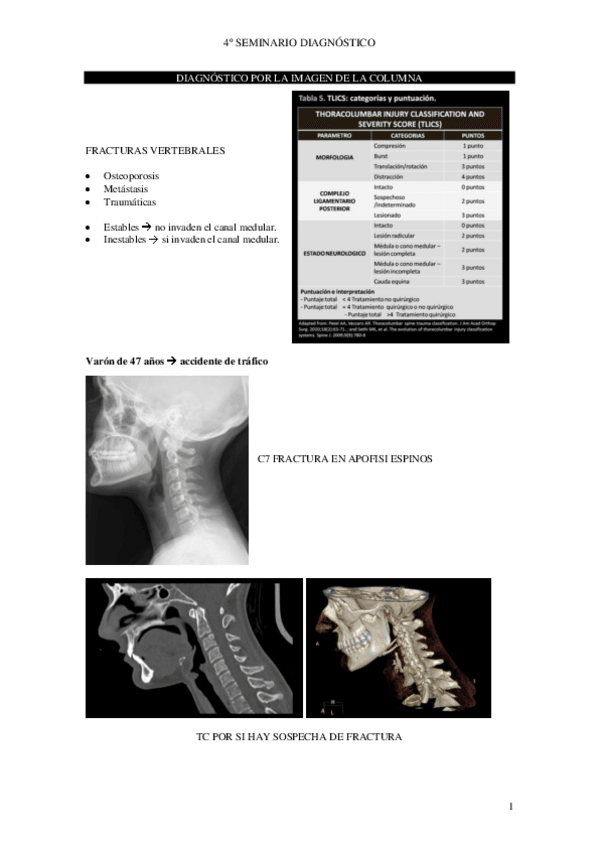

Practica-5-Columna-Vertebra-Anatomia-patologica.pdf

Practica-6-Osteomuscular-fracturas-luxaciones.pdf